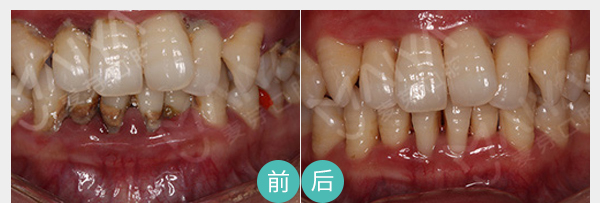

麦芽EMS洁牙

麦芽EMS洁牙将超声波洁牙、喷砂洗牙双重洗牙技术二合一,30分钟给你舒适的体验,清洁口内牙菌斑及其附着的牙结石。

适应症:牙周炎